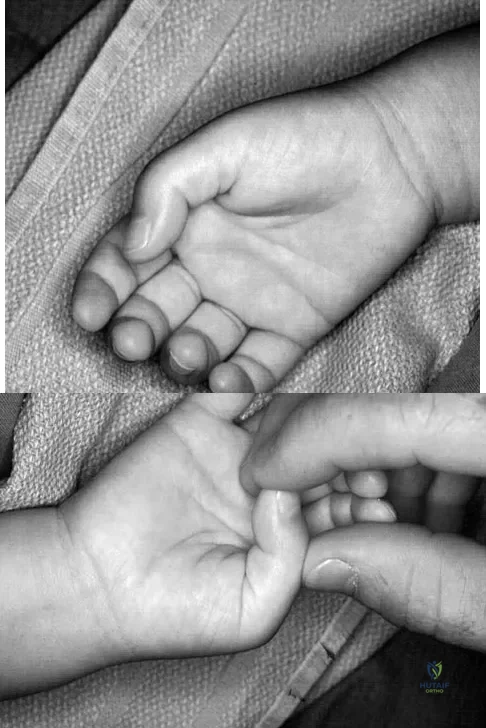

A 6-year-old child has a fixed flexion deformity of the interphalangeal (IP) joint of the right thumb. The thumb is morphologically normal, with a nontender palpable nodule at the base of the metacarpophalangeal joint. Clinical photographs are shown in Figures 42a and 42b. Based on these findings, what is the treatment of choice?

Explanation